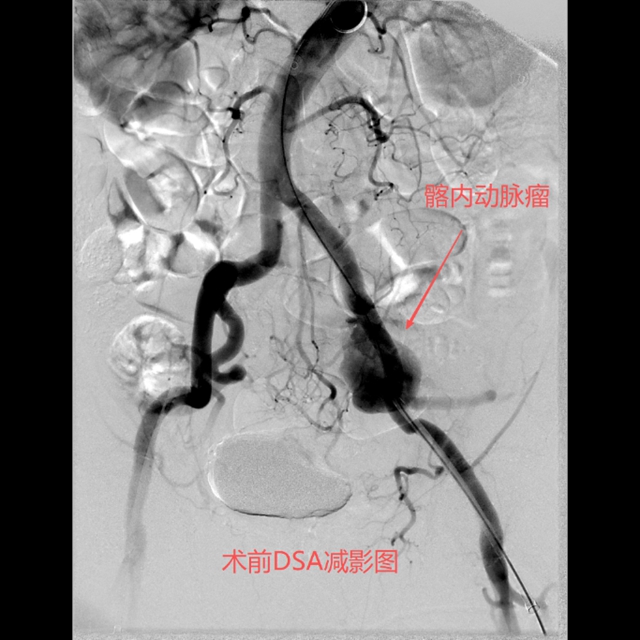

术前